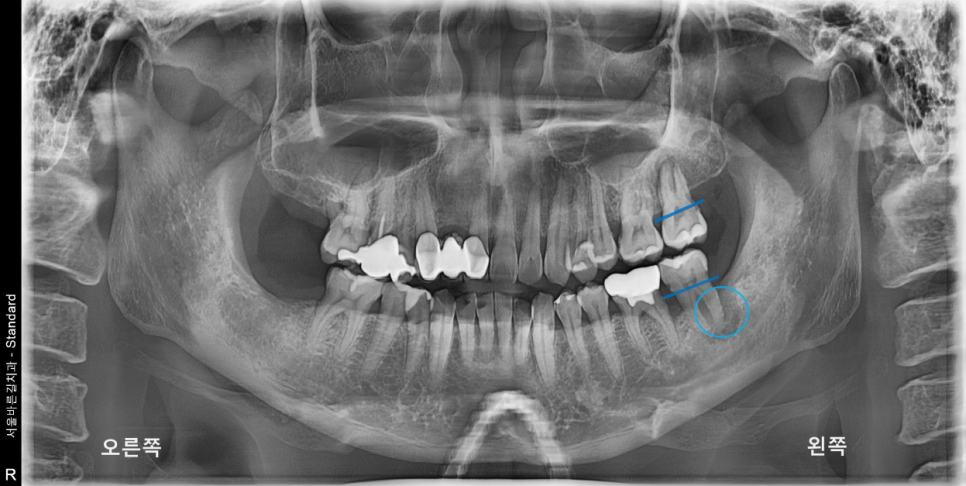

환자분께서 불편해 하시는 왼쪽 위, 아래로

표시해둔 부분처럼 수평적 및 수직적으로

골소실 되어있음을 확인 할 수 있었습니다.

제가 동그라미 친 곳을 보시면 치아 주변에 까만 양상이 보입니다.

염증에 의해 잇몸이 소실되어 방사선 투과성이 생겨

까만 형태로 엑스레이에 보이는 상황입니다.

치조골이 전반적으로 소실되어

치아 뿌리 끝의 치조골만으로 유지되고 있었습니다